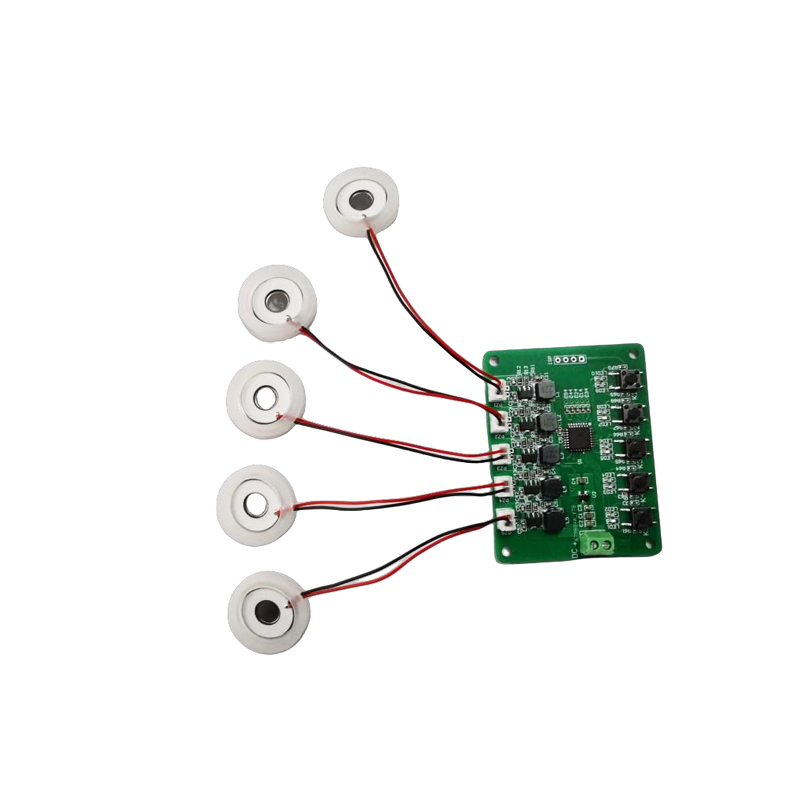

أقراص البخاخات الشبكية الطبية هي مكونات دقيقة تستخدم في الأجهزة الطبية لتحويل الأدوية أو المحاليل إلى جزيئات صغيرة من الهباء الجوي لعلاج اضطرابات الجهاز التنفسي المختلفة مثل الربو ومرض الانسداد الرئوي المزمن (COPD) وما إلى ذلك عن طريق الاستنشاق. يعد التصميم واختيار المواد لطبقة البخاخات أمرًا بالغ الأهمية لضمان توصيل الدواء بشكل فعال وراحة المريض. يتم ثقب ورقة الحجاب الحاجز غير القابل للصدأ بآلاف من الثقوب الشبكية الصغيرة مقاس 2-3 ميكرومتر في الصفائح الفولاذية من خلال تقنية الحفر بالليزر في عملية ليزر دقيقة، ومن ثم يتم ربطها بإحكام مع الصفائح المستديرة الخزفية الكهرضغطية، والتي تحول تردد الرنين للصفائح الكهرضغطية إلى طاقة اهتزاز عالية التردد من خلال إشارة الخرج للوحة تشغيل PCB، وتكسر بسرعة الدواء السائل إلى جزيئات الهباء الجوي الدقيقة. وتسمى هذه القطرات أيضًا بحجم الجسيمات المتوسطة، عندما تصل نسبة حجم الجسيمات المتوسطة D50 إلى> 60% أو أكثر، ستكون الجسيمات صغيرة بما يكفي لتتمكن من الوصول إلى عمق الرئتين إلى سطح الحويصلات الهوائية مع التنفس، وبالتالي تحسين كفاءة امتصاص الدواء والتأثير العلاجي. تحتوي صفائح البخاخات الشبكية الطبية الدقيقة بشكل أساسي على عدة أشكال، ورقة البخاخات الشبكية الدقيقة المصنوعة من الفولاذ المقاوم للصدأ، ورقة البخاخات الطبية بالنيكل والبلاديوم، ورقة البخاخات الطبية بوليمر PI، وما إلى ذلك. كل ما سبق يتم من خلال تحويل طاقة الاهتزاز الخزفي الكهرضغطي لتحقيق تأثير الانحلال.

رذاذ الموجات فوق الصوتية هو جهاز يستخدم مبدأ الاهتزاز بالموجات فوق الصوتية (تحويل الطاقة) لتحويل السائل إلى قطرات صغيرة. مبدأ العمل هو الخواص الكهرضغطية الفريدة للسيراميك الكهروإجهادي للقرار، قطعة الانحلال في استلام مطابقة إشارة المجال الكهربائي، ستنتج تردد التذبذب المقابل، من خلال دور الاهتزاز عالي التردد للتجويف السائل الذي يتم التخلص منه بعيدًا عن سطح الماء لإنتاج نوع من جزيئات ضباب الماء، متناثرة مع عدد كبير من الأيونات السالبة وجزيئات صغيرة من الجزيئات، يمكن تحقيق زيادة في الرطوبة المحيطة، ودور الهواء النقي. سطح الرذاذ مطلي بالمينا الزجاجية عند درجة حرارة عالية تصل إلى 800 درجة لحماية الأقطاب الفضية للصفيحة الكهرضغطية، وزيادة مقاومة الأحماض والقلويات ومقاومة الأكسدة للرذاذ، وزيادة عمر خدمة الرذاذ. يستخدم على نطاق واسع في أجهزة الترطيب الداخلية وأجهزة تنقية الهواء وعلاج البخاخات الطبية وسيارات التجميل وغيرها من المجالات، ولكنه مناسب أيضًا للمستودعات والمصانع والترطيب والتطهير لخلق جو من معدات الترطيب. تستخدم أقراص الضباب بشكل رئيسي في الترطيب الصناعي، والتعفير الطبي، والتعفير بالروائح العلاجية، والترطيب البيئي، وضباب الحديقة وغيرها من المشاهد.